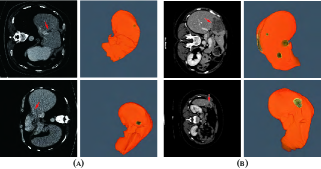

Refer to caption

Figure 1: Examples of typical 2D CT scans and 3D views of the corresponding ground truth of liver/tumor extractions where red arrows indicate the tumor/lesion regions. The orange regions denote the liver, and the darker regions within the yellow regions denote the tumors. (a) shows two slices from the MICCAI 2017 Liver Tumor Segmentation (LiTS) dataset. (b) shows two slices from the 3DIRCADb dataset.